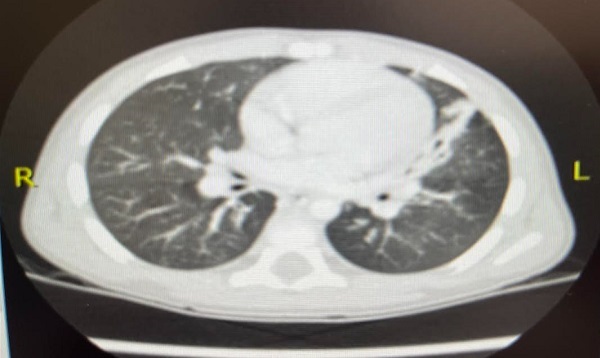

Dada la recurrencia de episodios, exploración alterada entre los mismos e imagen radiológica persistente, se realiza analítica sanguínea que incluye perfil inmunológico sin hallazgos y se remite a Respiratorio Infantil, donde se realiza tomografía axial computarizada (TAC): hallazgos sugestivos de proceso infeccioso broncoalveolar; atelectasia paracardiaca en língula (Figura 4).

Figura 4. Hallazgos sugestivos de proceso infeccioso broncoalveolar; atelectasia paracardiaca en língula